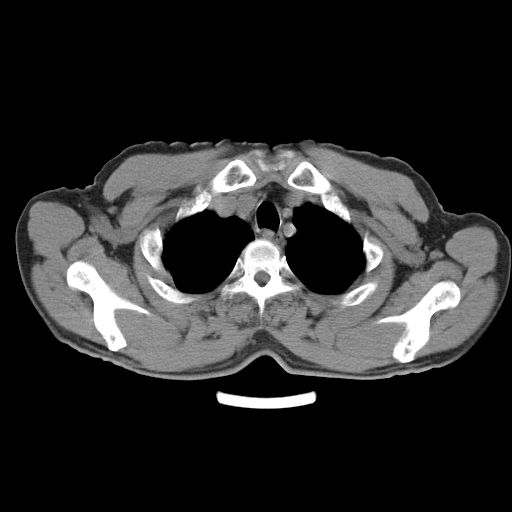

以下是引用心路寻觅在2010-3-1 10:23:00的发言:[br]1、考虑左肺上叶周围型肺癌[br]2、右上肺陈旧性病灶。[br][br][本贴已被 心路寻觅 于 2010-3-1 10:40:18 修改过]

以下是引用shuiyuan在2010-3-1 10:45:00的发言:[br]考虑左肺上叶中心型肺癌伴阻塞型炎症,邻近胸膜受侵。